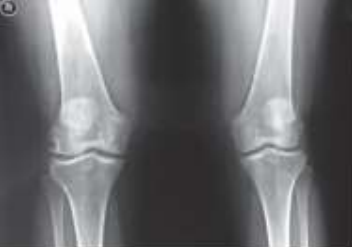

A osteoartrite (OA) é a mais frequente das artrites, sendo causa importante de incapacitação decorrente de dor e/ou destruição articular, com grande custo pessoal e social. Observe as alterações típicas de osteoartrite na imagem a seguir.

Radiografia de joelho com osteoartrite.